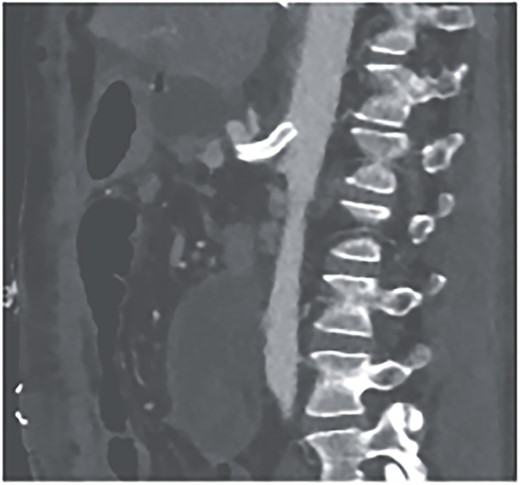

A 52-year-old otherwise healthy patient was admitted to the emergency room of our hospital with an acute abdomen and hemodynamic instability. The computed tomography (CT) angiography revealed an active, most likely aneurysmal bleeding of the pancreaticoduodenal artery with venous pooling, along with a large retroperitoneal hematoma measuring ~2000 ml in volume (Fig. 1). Due to hemodynamic instability and the unavailability of interventionalists, the decision for emergent exploratory laparotomy was made. Intraoperatively was a ballooned and hemorrhagic retroperitoneum with incipient perforation of the mesenteric root observed. To gain exposure, an extended Kocher maneuver according to Cattell–Braasch was performed, necessitating a rightsided hemicolectomy. The bleeding was managed by ligating the pancreaticoduodenal artery. An Easy-Flow drainage was placed, and a split stoma was created. Intraoperatively, due to an estimated blood loss of over 4 L, transfusion therapy was administered following a massive transfusion protocol, along with extensive coagulation correction.

CTA showing an active bleeding likely from the pancreaticocuodenal artery with venous pooling and a large retroperitoneal hematoma.